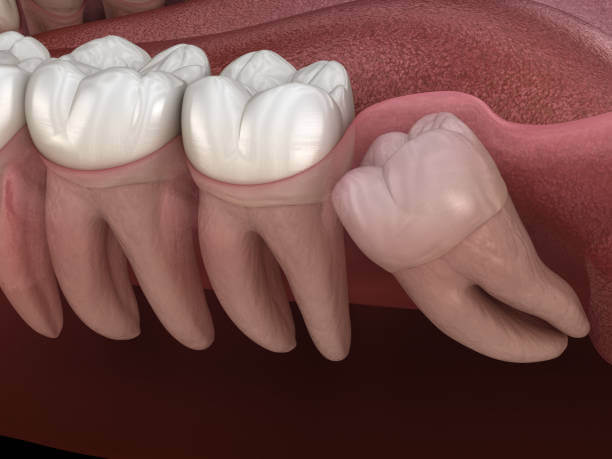

인류의 턱이 작아지면서 입안 깊숙이 사랑니가 자랄 공간이 부족해졌고 이 때문에 사랑니는 눕거나 발치하는 등 썩거나 염증이 생기기 쉬운 모양으로 나오는 경우가 많습니다.

사랑니는 다른 치아에 비해 크기와 모양이 매우 다양합니다. 사랑니는 똑바로 나오지 않고 기울어져 있거나 누워있는 경우 잇몸에 묻혀 있는 부분이 많습니다.

이 때문에 음식물 찌꺼기가 잇몸과 사랑니 사이에 끼기 쉽고 칫솔이 사랑니에 잘 닿지 않아 썩는 경우가 많고 제대로 청소하지 않으면 세균이 번식하고 염증이 생기기 쉬운 상태가 됩니다.